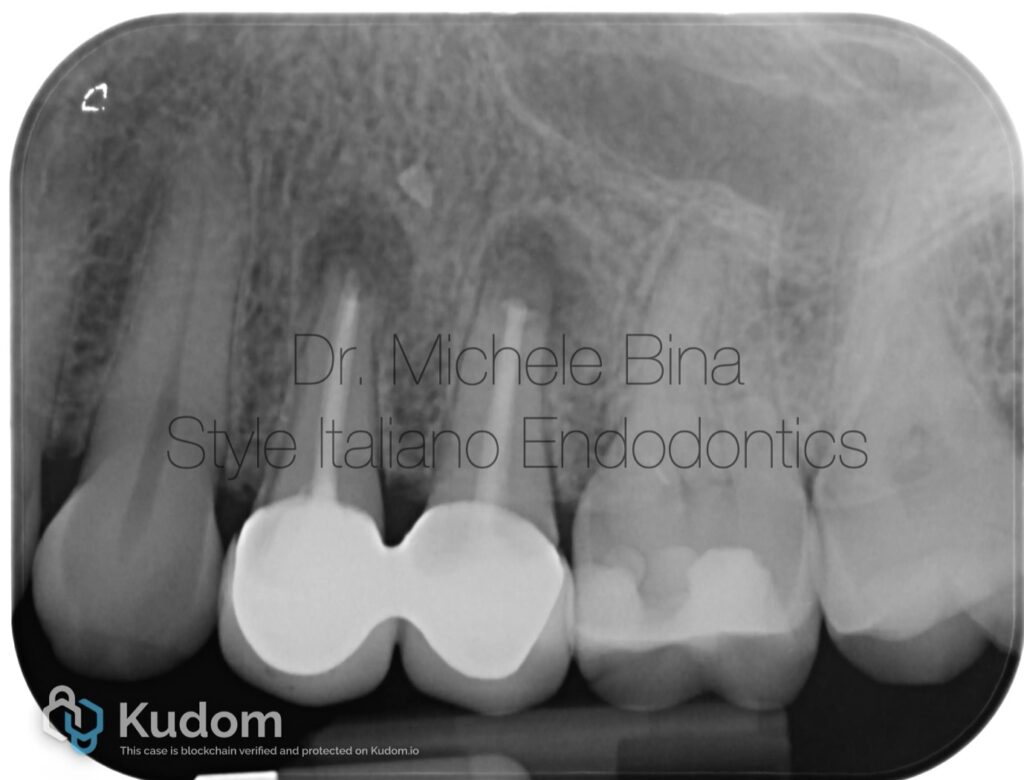

Fig. 1

Patient M.V., in good systemic health, presented with symptomatic apical periodontitis affecting teeth 2.4 and 2.5 after failed previous surgical endodontic treatment. Tooth 2.4 showed a sinus tract, indicating persistent infection.